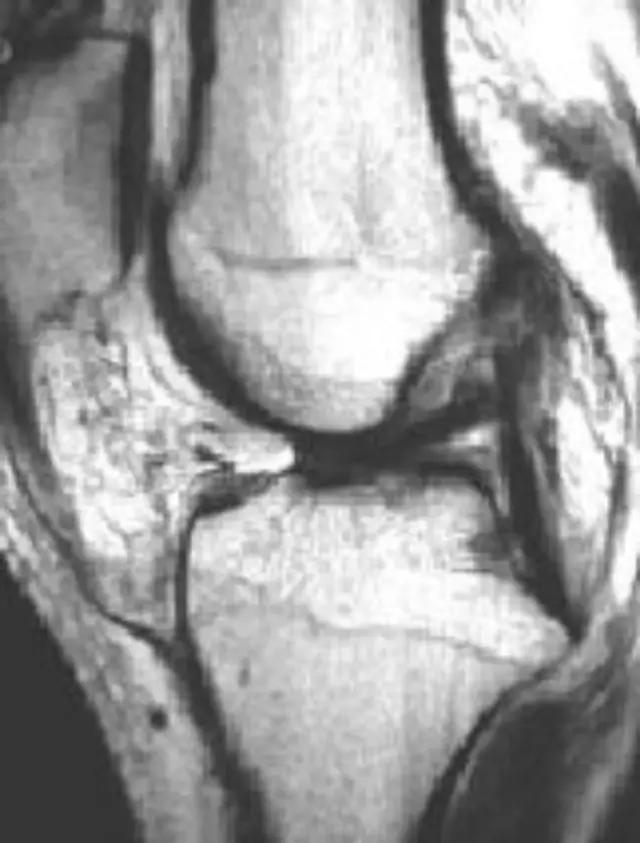

临床上以常见病为主,疑难病人不多,如果我们一下子就往疑难方面去想,反而容易进入死胡同。 病例:杨XX,男,25岁,右髋关节反复肿痛,逐渐丧失行走功能20年。辗转完国内著名医院就诊未果。只能考虑:慢性炎症?

所有改变尽量用最少疾病解释——

这种诊断思路值得学习,但医生并不真正了解膝关节OA,本病人髌骨的信号改变是骨性关节炎的病理改变之一,而不是骨肿瘤!